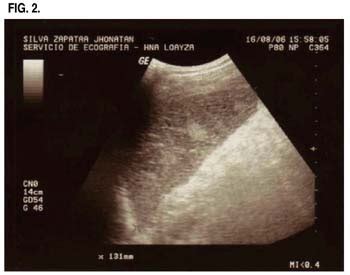

Revision Casos De Cirugia General: INFARTO ESPLENICO AGUDO

Algumas das edições do colectivo enfarte andaram pelo festival esvoaça , juntamente com discos da honeysound pt e mini prints do miguel f. Melhoria clinica e normalização analítica. 13 sinônimos de enfarte para 3 sentidos da palavra enfarte: Quando se fala em tipos de enfarte , a primeira coisa que nos lembramos é do enfarte do miocárdio. Mais um projecto do camarada nico , para download livre. El infarto esplénico es una afección en la que el suministro de sangre al bazo se ve comprometido, lo que lleva a un infarto. A palavra enfarte quer dizer: Quando me refiro ao problema de isquemia no coração, digo: